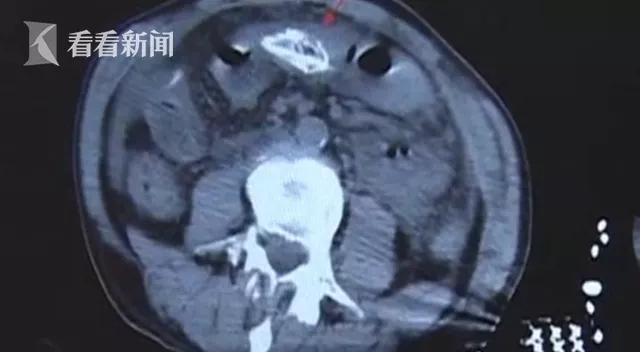

医生介绍道,该男子前来就诊时表情痛苦、心情烦躁,再加上其血压下降,表现为感染性休克。医生通过腹部CT检查初步判断他的腹腔有异物。

随着时间的推移,这名男子已经疼得无法与人正常交流了。医生根据他的症状、体征,结合腹部CT检查,判断为消化道穿孔。通过腹腔镜探查,医生这才看清,男子腹中的异物竟然是一条黄鳝!

主治医生表示, 黄鳝进入了患者的腹腔后已经死亡,致该患者的腹腔污染非常严重, 有大量淡绿色的渗液,腹壁、肠道、肝脏等多处附着大量的脓苔和粪便。 可以确定患者是黄鳝所导致的“乙状结肠破裂”。